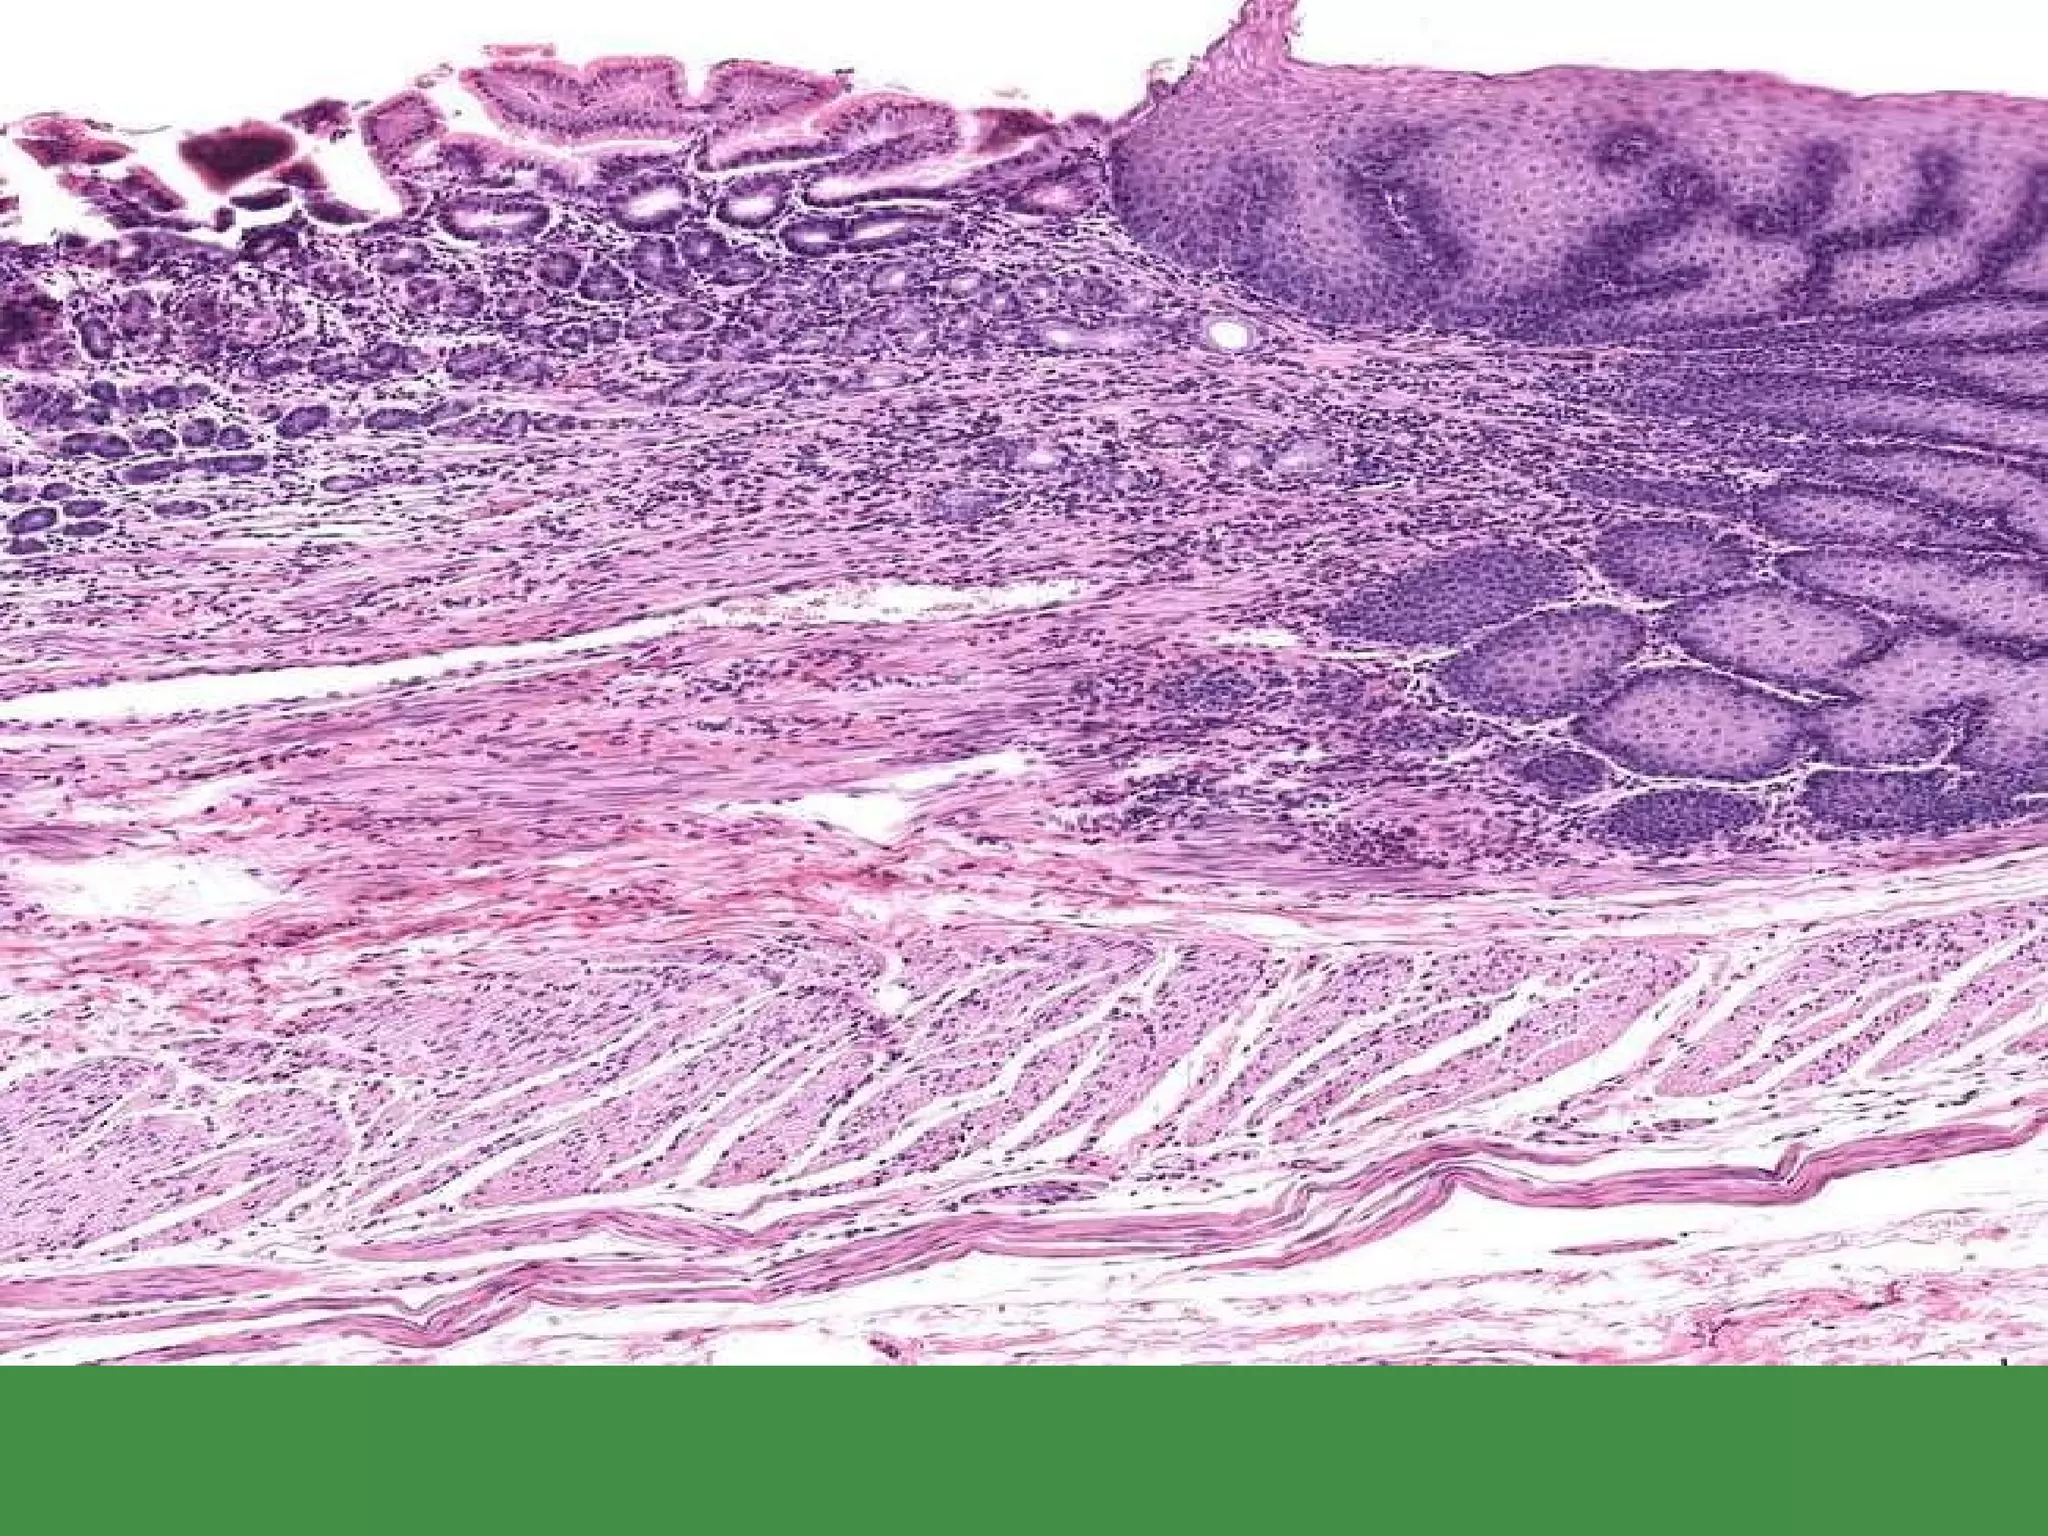

CELIAC DISEASE Also called SPRUE Also called NON-tropical SPRUE Also called GLUTEN-SENSITIVE ENTEROPATHY Sensitivity to GLUTEN, a wheat protein, gliadin Immobilizes T-cells Also in oat, barley, rye Progressive mucosal “atrophy”, i.e. villous flattening Relieved by gluten withdrawal

CELIAC DISEASE

CELIAC DISEASE Alsocalled SPRUE Also called NON-tropical SPRUE Also called GLUTEN-SENSITIVE ENTEROPATHY Sensitivity to GLUTEN, a wheat protein, gliadin Immobilizes T-cells Also in oat, barley, rye Progressive mucosal “atrophy”, i.e. villous flattening Relieved by gluten withdrawal

• #125 Mucosal (villous) flattening and chronic mucosal inflammation